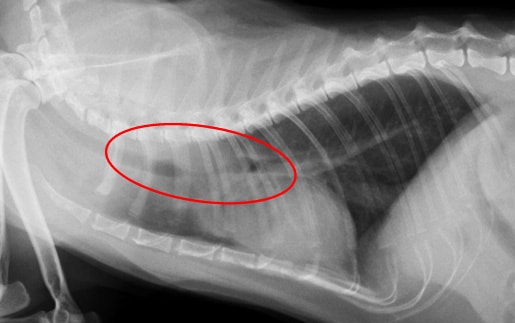

気管内に発生した腫瘍により呼吸困難を呈し、開胸減容積手術により呼吸改善がみられた一例

来院時のレントゲン胸部レントゲン写真です。 |